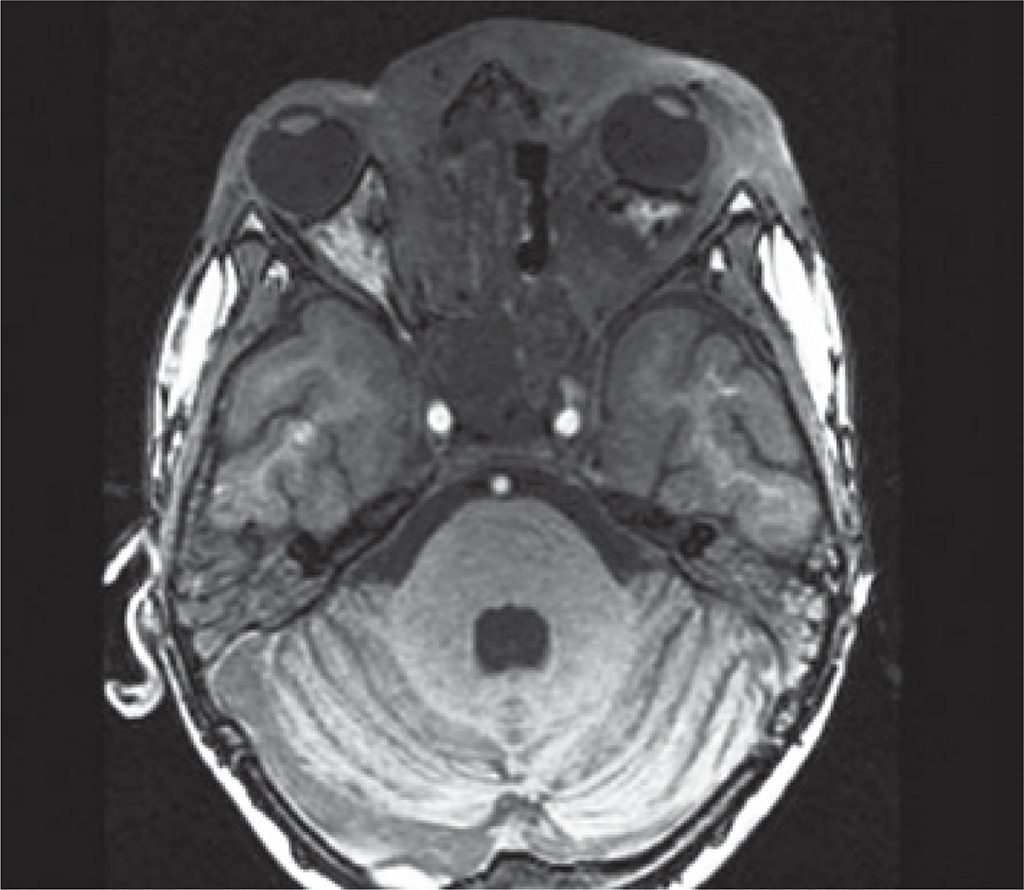

Figure 5

Decreased infiltrative lesion that affects the subcutaneous tissue, mainly in the left periorbital region and reduction of proptosis at the same side. Lesion reduction in nasopharynx, hypopharynx and sinuses, compared to previous images